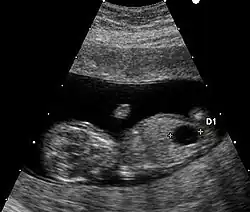

Les anomalies échographiques sont également prises en compte. Il s'agit de la recherche de malformations classiques de la trisomie 21 (comme les malformations cardiaques) et aussi de «marqueurs dont le plus important est l'épaisseur de la clarté nucale. D'autres signes sont discutés car difficiles à mesurer avec des résultats variables selon les observateurs. Toutefois, à la fin des années 2000, la combinaison entre la mesure de la clarté nucale et l'âge maternel est considérée comme un marqueur puissant d'une probabilité de trisomie 21[40].